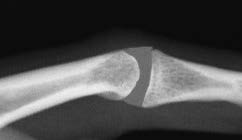

*X線検査

X線検査では、骨の破壊は判りますが、滑膜は判らず、初期の骨びらんも判りにくい場合があります。

グレーの部分が滑膜になりますが、X線検査では滑膜は写りません。